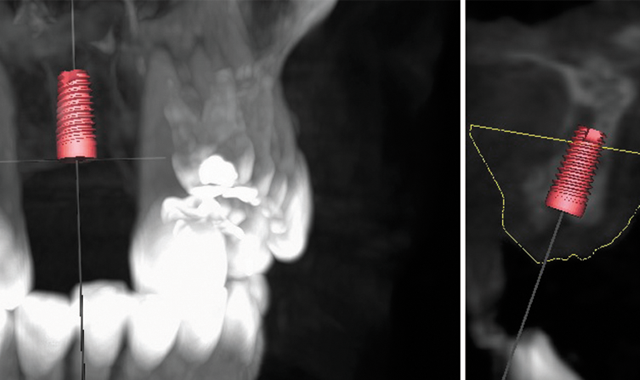

Fig. 1 Implant alignment in the CBCT scan.

Once the intraoral scan of the patient’s mouth or scanned models have been imported and aligned in the surgical guide fabrication software, a rough implant placement is done using the information on the Rx and industry-standard guidelines. Vital structures are able to be visualized on the scan, and are then accurately marked by an Albensi technician. The treatment plan is then reviewed by resident periodontist Dr. Michael Pikus and is approved or adjusted accordingly.

Dr. Pikus always evaluates implant angulation and the esthetic goals of the case. Bone density and vital structures are evaluated and implants placed in the most ideal position given the patient’s oral anatomy and pathology (if any is noted). Implant size and restorative options are considered so that spacing of implants is proper to achieve proper balance and cross arch stabilization to maximize implant and immediate load stability. Upon completion of the internal review, a remote session is scheduled between the dentist and an Albensi Laboratory specialist where the plan is reviewed and final adjustments requested by the treating dentist can be made.